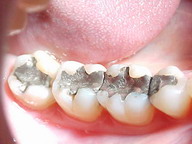

ANTES DEPOIS

O caso acima ilustra uma substituição de restauração de amálgama por um INLAY Artglass ( 1º molar) e restauração em resina composta no 2º molar.